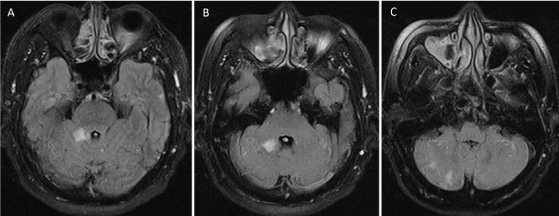

After embolization, the patient has gradually recovered and could get back to the activities of daily living at home. Two years after the endovascular treatment, the right vertebral angiography confirmed complete obliteration of the fistula (Figure 6). During a follow-up period of 3 years, the patient had no further recurrent embolic events and was placed only 81 mg of aspirin once daily. There were no new lesions at the follow-up imaging studies. However, his impairment of recent memory has still persisted. He was diagnosed as vascular dementia and donepezil 5 mg per day has been continued for this symptom.

Figure 6. Anteroposterior (A) and lateral (B) of the right vertebral artery injection obtained 2 years after the endovascular treatment with coils confirm nearly complete obliteration of the fistula AVF